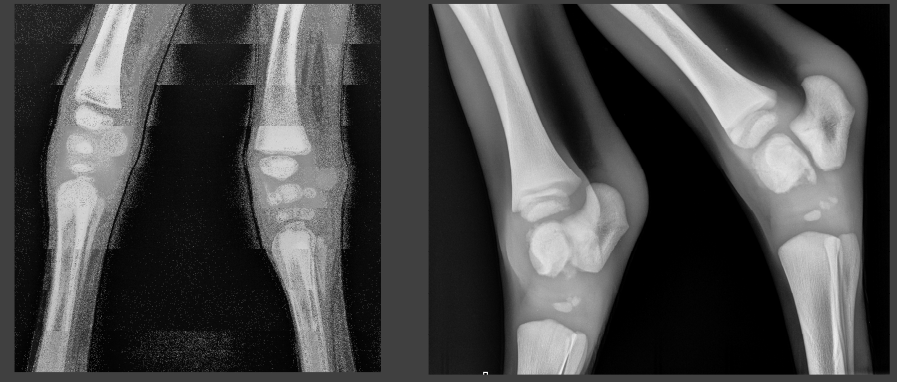

tarsal OCD fragment

incomplete ossification in a young animal

dysmature foal with underdeveloped joints

needs casts/splinting, 24 hour care for 2 months